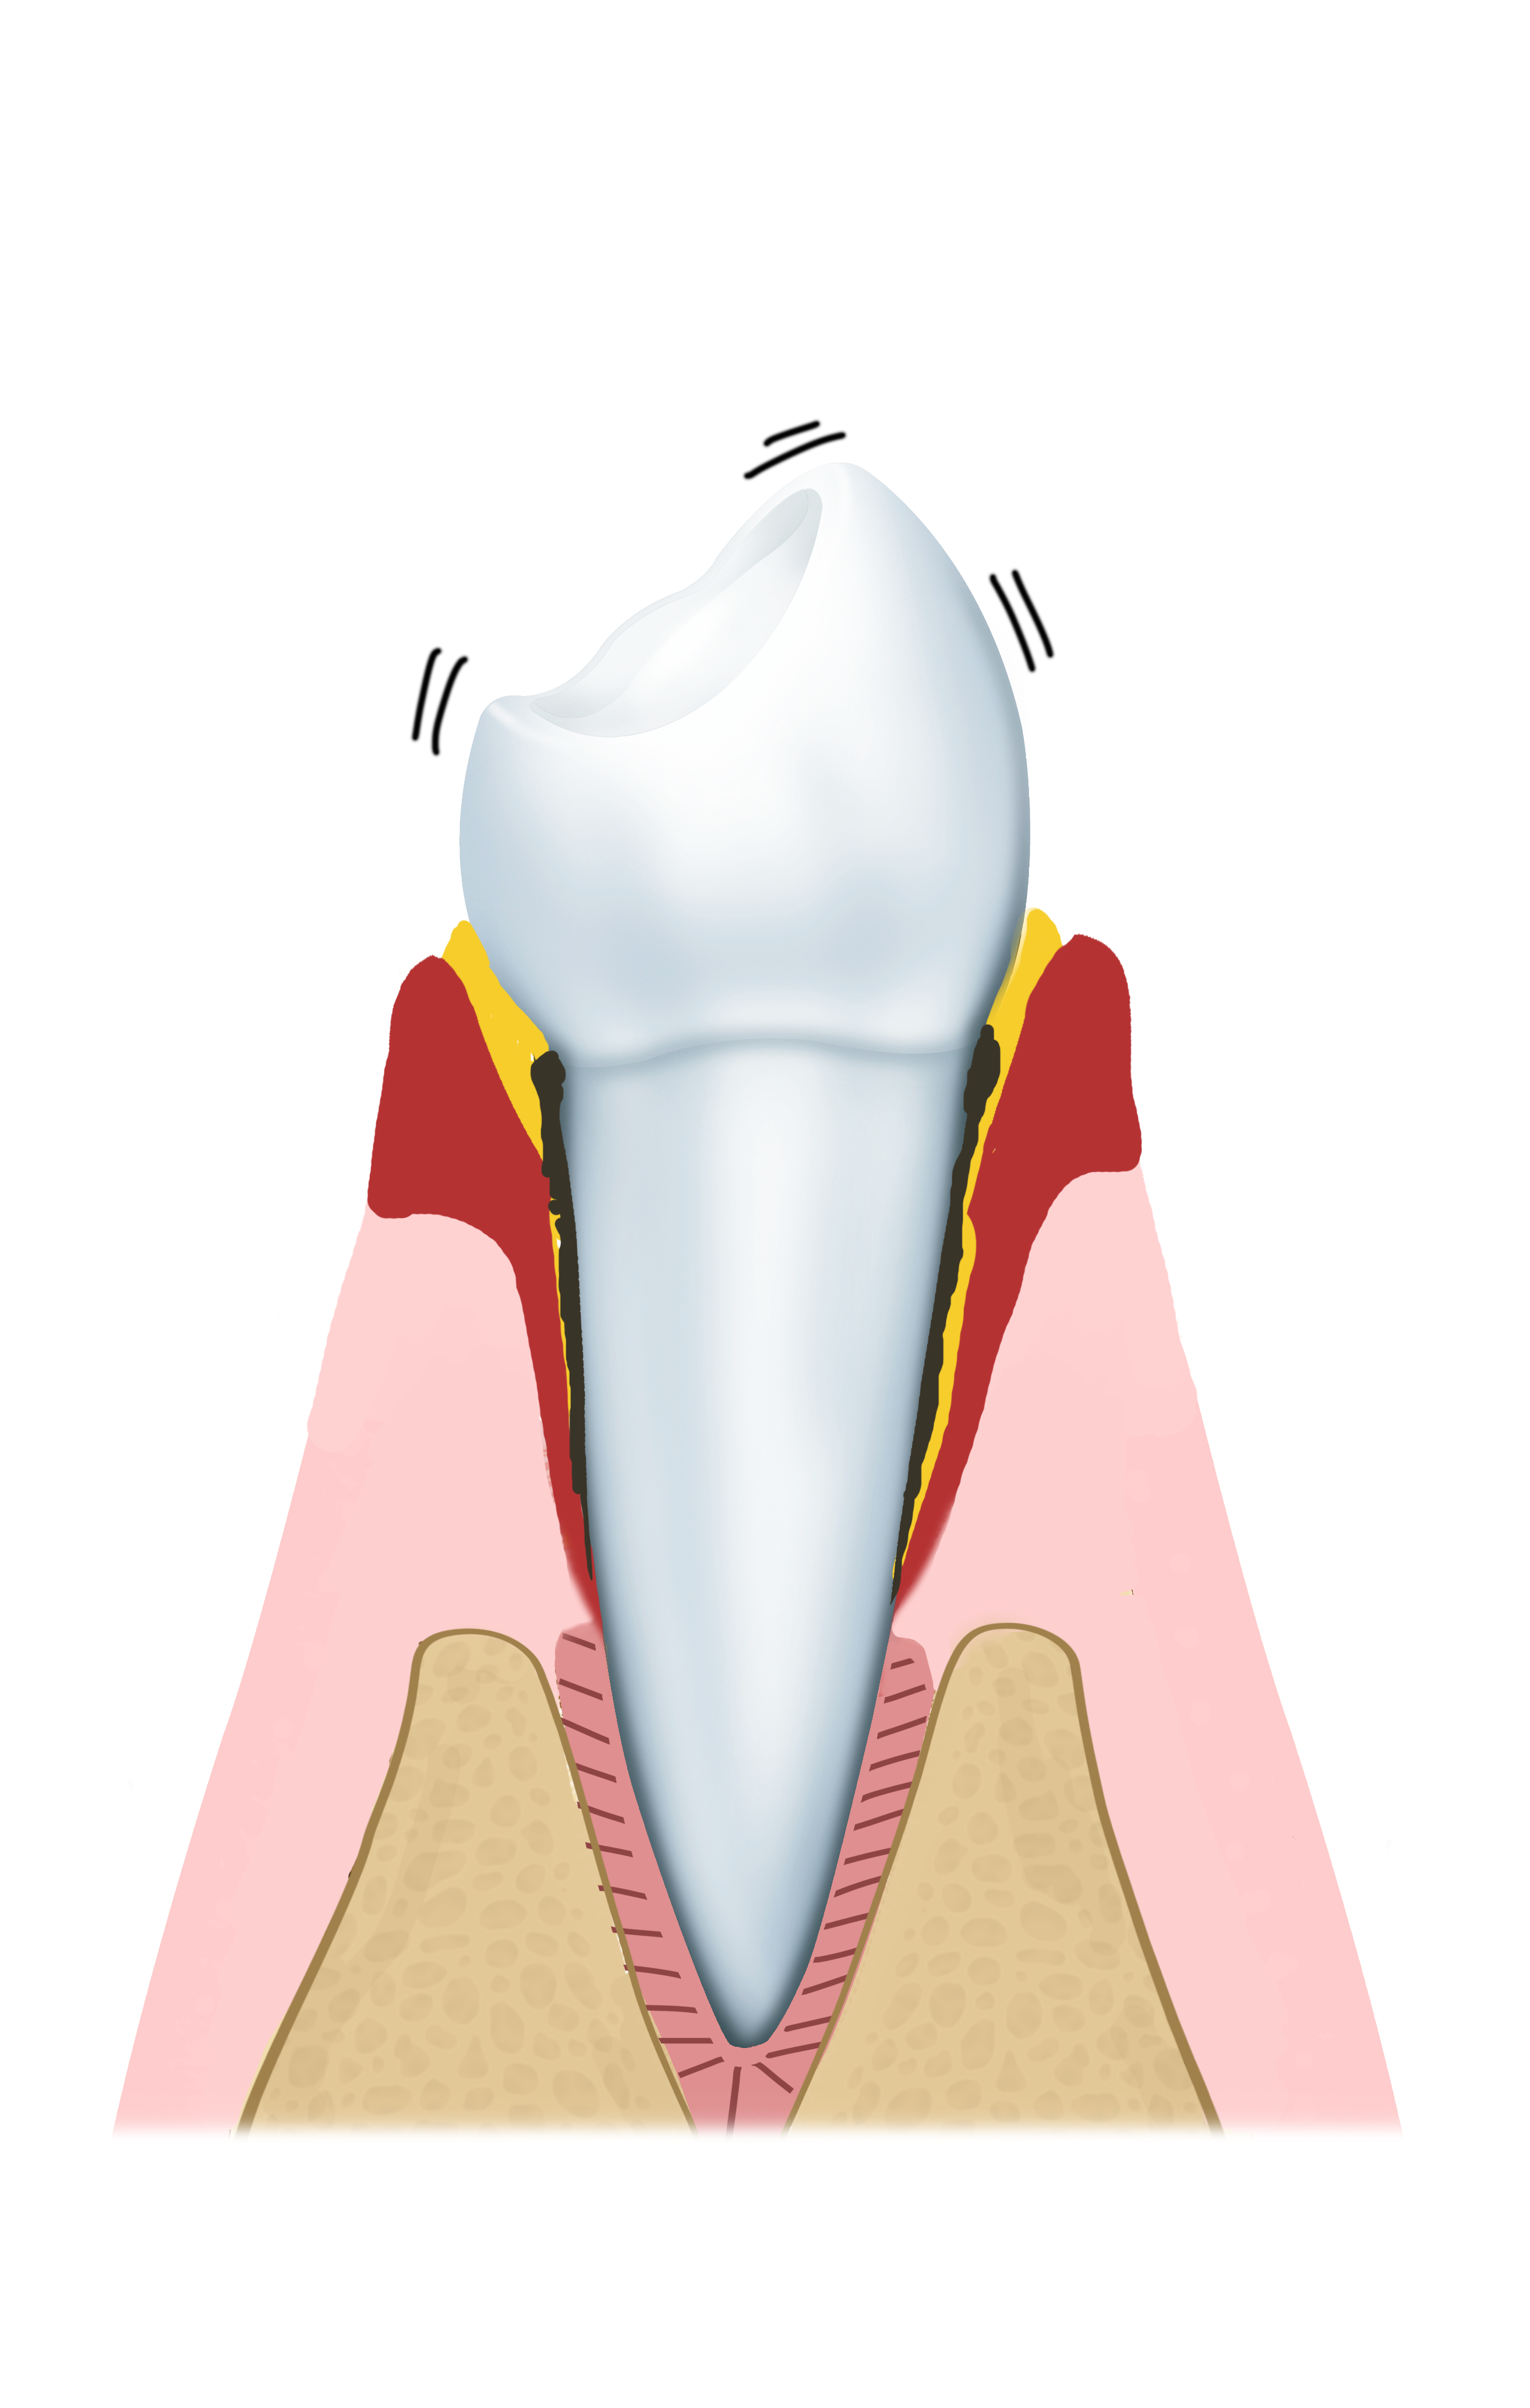

Stadium 2: Parodontitis

Bij parodontitis breidt de tandvleesontsteking zich uit naar de rand van het tandvlees en/of het kaakbot. Het kaakbot kan worden aangetast waardoor tanden en kiezen los gaan zitten of zelfs uitvallen.

Parodontitis gaat niet vanzelf over. Om dit te genezen zal er een paro-protocol moeten worden opgestart. Onze tandarts of mondhygiënist geeft u graag gedetailleerder advies.